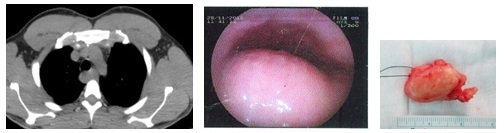

25. Otuzbir yaşında

erkek hasta, disfaji şikayeti mevcut, toraks BT kesiti, özofagoskopik görüntüsü

ve ameliyat piyesi altta olan bu hastada hangi patolojiyi düşünürsünüz?

a)

Özofagus

kanseri

b)

Bronkojenik

kist

c)

leiomyomu

d)

divertikülü

e)

Nörojenik

tümör